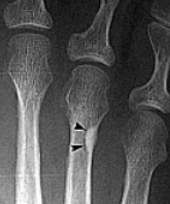

What disease is this? What do the arrows indicate? | Gout Arrows = 'punched out' erosions |